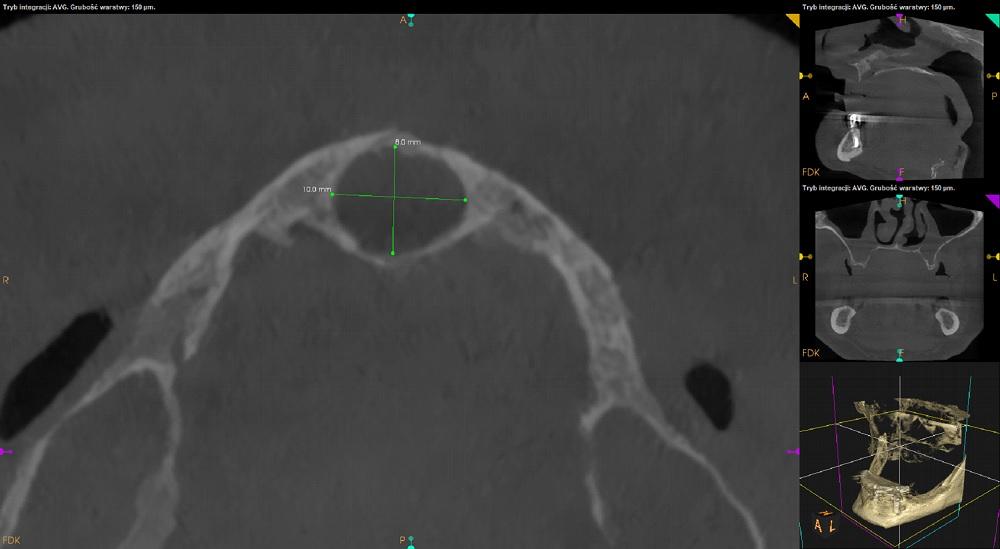

Tomografia szczęka i żuchwa.

Szczęka.

Kostna przegroda nosa skrzywiona w lewą stronę z kolcem. Zatoka szczękowa prawa niepowietrzna w około 1, lewa w około 2 swojej objętości.

Bezzębie. Zaawansowany zanik wysokości wyrostka zębodołowego szczęki.

Pozostawione fragmenty korzeni zębów 16 i 14.